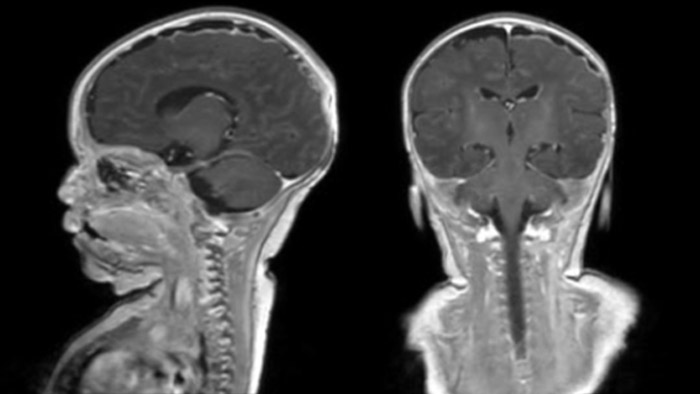

Hydrocephalus post hemorrhagic Both pictures show a ventriculoperitoneal shunt. With our previous scanner our hydrocephalus protocol needed about 25 min. With Ambition the examination time is about 14 min. including a CSF PCA sequence to show flow in the aqueduct.

Dural sinus malformation (DSM) Initial examination

After three times of coiling and acryl based embolization